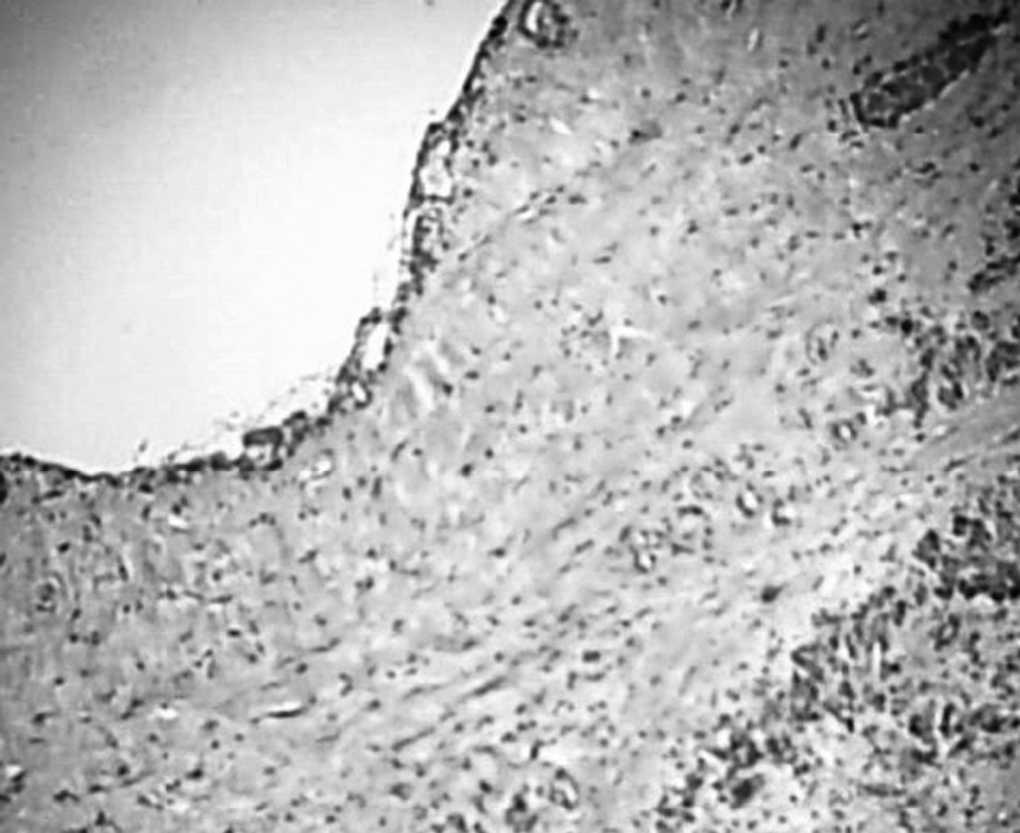

Fig. 3. Cistoadenoma seroso pancreático oligoquístico. Obsérvese una formación quística unilocular. Por debajo del epitelio de revestimiento podemos apreciar tejido fibrótico y de granulación. El parénquima pancreático vecino muestra signos de pancreatitis crónica inespecífica (extremo inferior derecho de la imagen). (HE, x40).